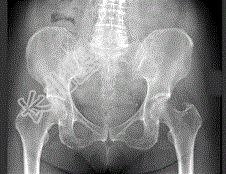

- 单项选择题女,67岁, 右髋和腹股沟痛6月余,结合图像, 最可能的诊断是